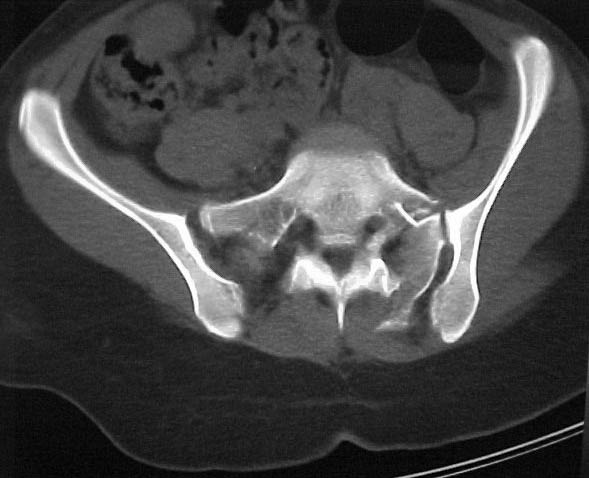

A 17 year old female involved in a car crash. Has a Type III lateral compression injury to her pelvic ring using the Young-Burgess classification. A windswept pelvis if you will. The images are included. There appears to be posterior displacement of the left hemipelvis as well.

Thanks for submitting your case to the forum, I am sure you will soon be toxic with recommendations that you will have to filter through. I would like to offer some rather elementary advice: Your patient needs to have appropriate inlet and outlet films adjusted for her anatomy;i.e.,she appears to be somewhat lordotic and that would require the gantry angle to be adjusted with each view. The same would be true for the CT scan it appears as though the angle of the gantry is tangential to the slope of the sacrum (sacro-horizontal line if you will) and that gives a distorted view of the posterior ring injury.